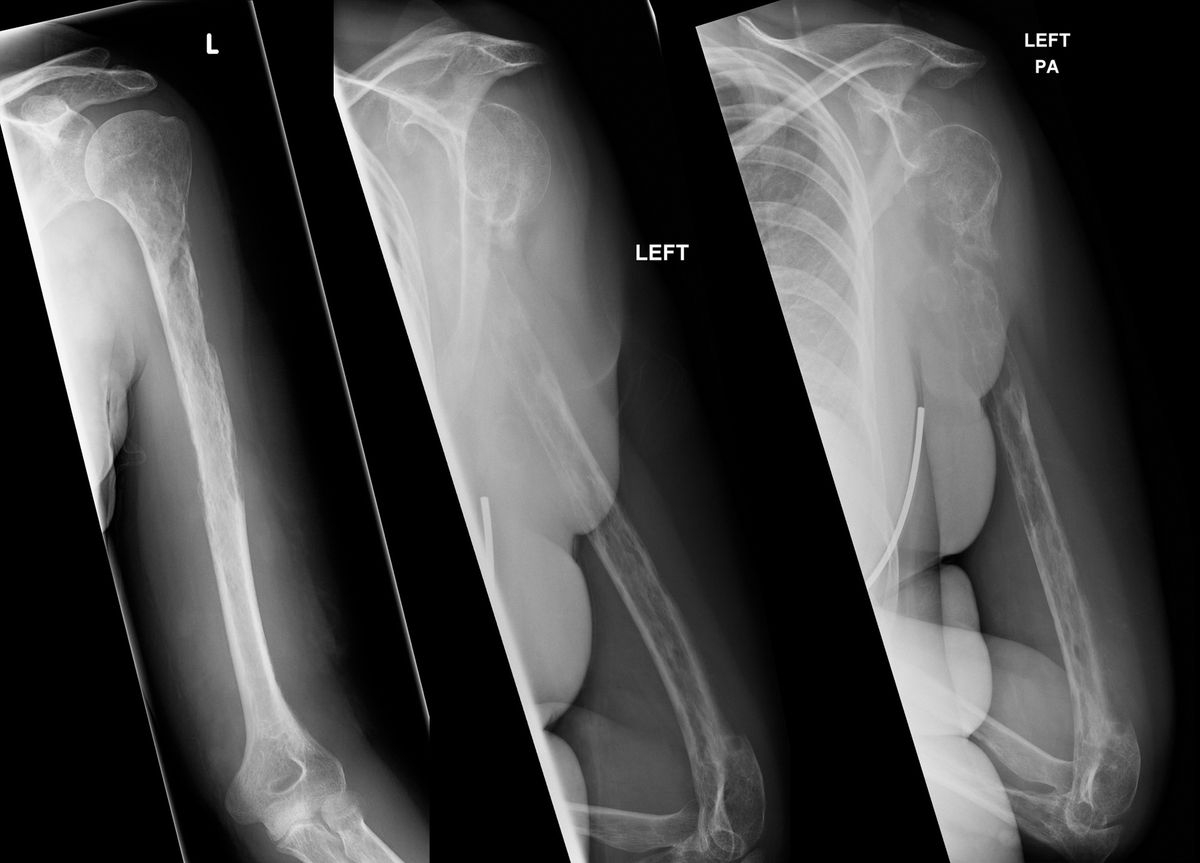

arm bone crossword clue

Target Arm Bone Crossword Clue: Humerus

Woman s Bones Vanish Before Doctors Eyes Live Science

Of An Arm Bone NYT Crossword Clue